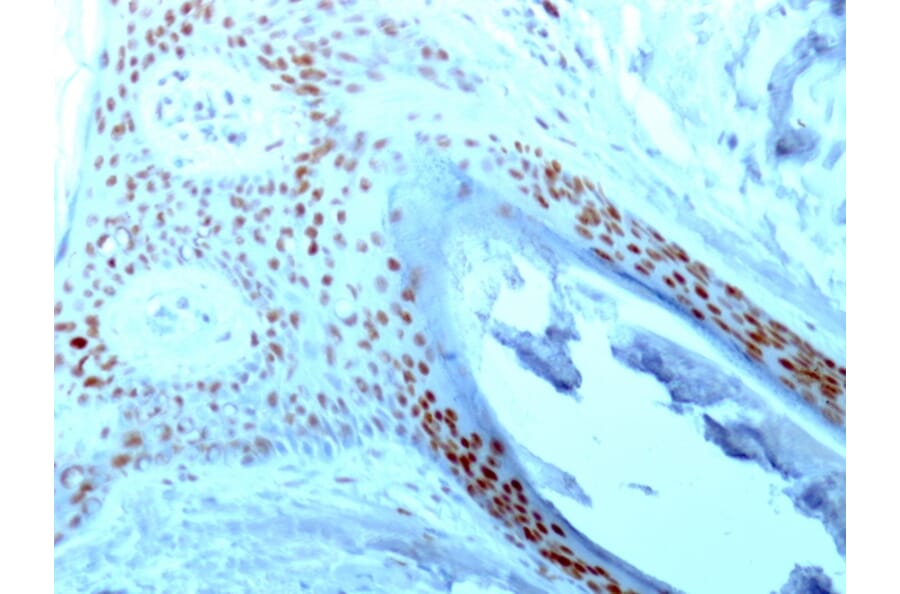

Specificity

This antibody recognizes a protein of ~76kDa, which is identified as Nucleolin (NCL). It is the major nucleolar phosphoprotein of growing eukaryotic cells. NCL is located mainly in dense fibrillar regions of the nucleolus. It is found associated with intranucleolar chromatin and pre-ribosomal particles. Human NCL gene consists of 14 exons with 13 introns and spans approximately 11kb. It induces chromatin decondensation by binding to histone H1. It is thought to play a role in pre-rRNA transcription and ribosome assembly.This MAb can be used to stain the nucleoli in cell or tissue preparations and can be used as a marker of the nucleoli in subcellular fractions. It produces a speckled pattern in the nuclei of cells of normal and malignant cells and may be used to stain the nucleoli of cells in fixed or frozen tissue sections. It can be used with paraformaldehyde fixed frozen tissue or cell preparations and formalin fixed, paraffin-embedded tissue sections.

Flow Cytometry, IF, WB, IHC-P

Flow Cytometry: 1-2 µg/million cells, IF: 1-2 µg/ml, WB: 1-2 µg/ml, IHC-P: 0.25-0.5 µg/ml